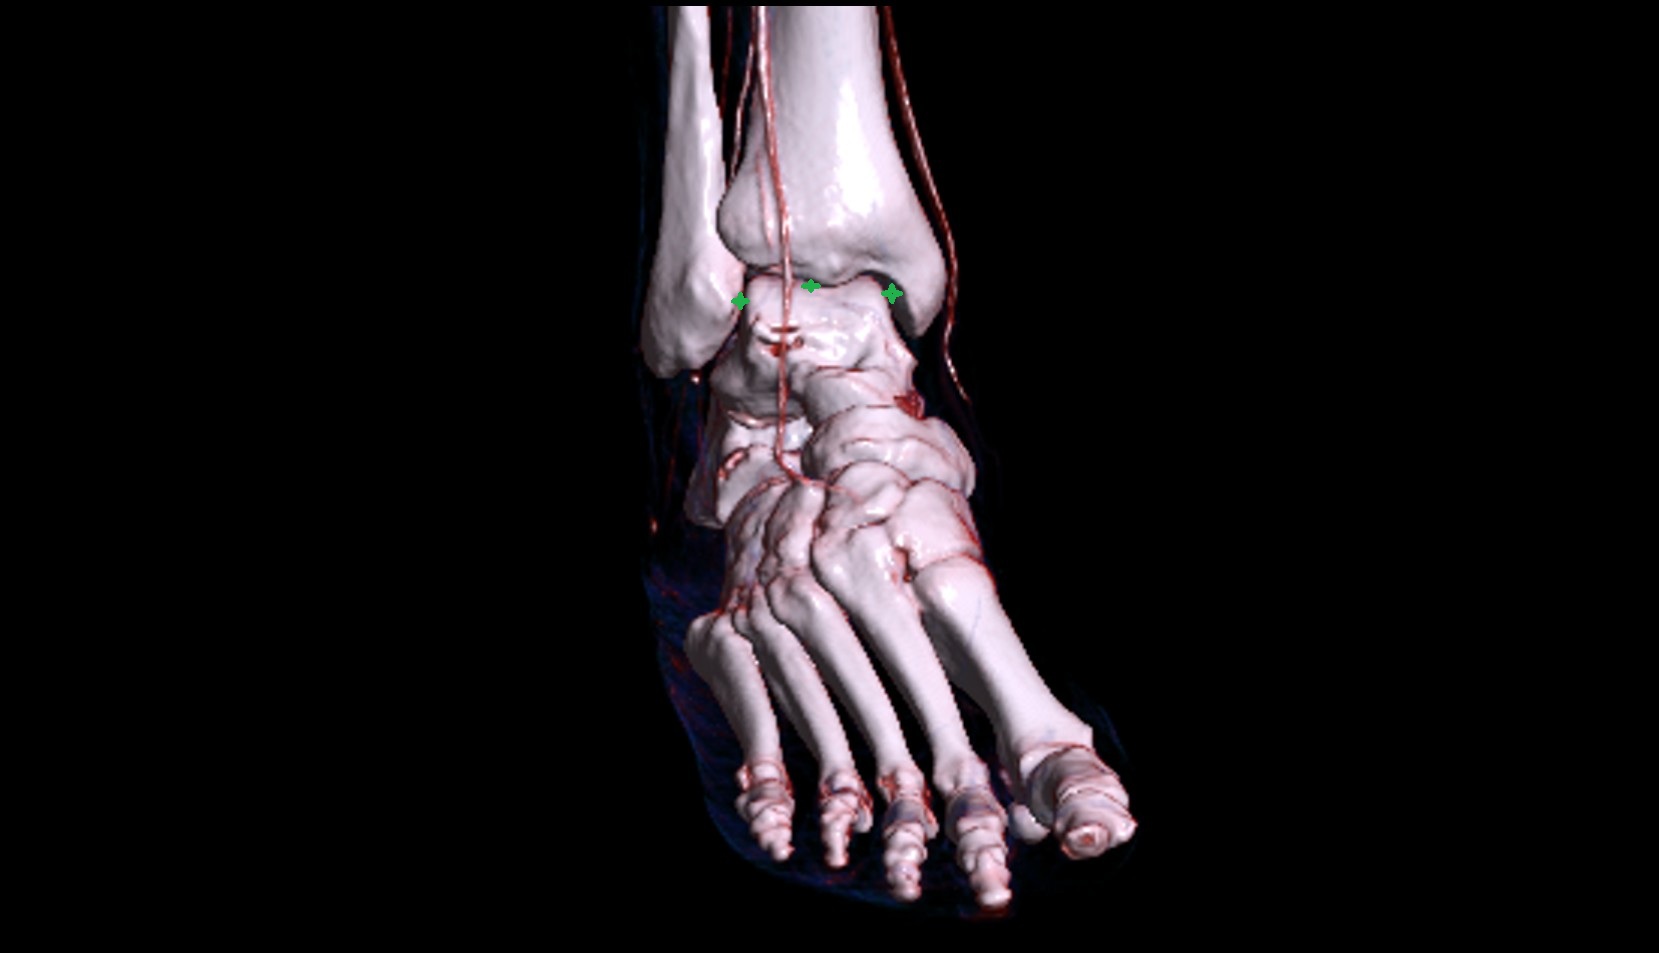

- Talus

- Head of talus

- Body of talus

- Neck of talus

- Calcaneus

- Ankle joint

- Talocalcaneal joint

- Talocalcaneonavicular joint